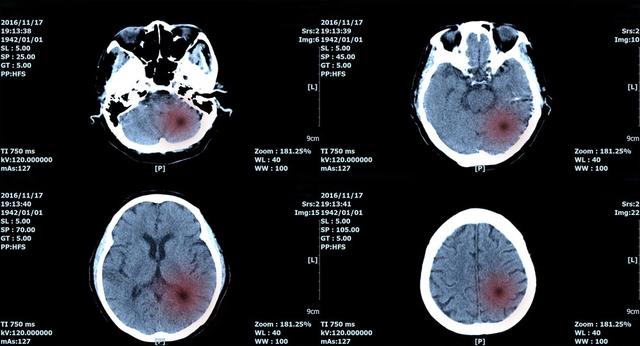

脑瘤是在大脑中生长的大量异常细胞。仅2016年,全球就有33万脑癌病例和22.7万相关死亡。早期发现对改善患者预后至关重要,多亏了一组研究人员,他们开发了一种新的成像技术和人工智能算法,可以帮助医生准确地识别脑瘤。

研究人员使用了一种新的成像技术,称为“拉曼光谱”(SRH),它可以揭示肿瘤在人体组织中的浸润。该技术收集分散的激光并强调在许多人体组织图像中不常见的特征。

对于这些新图像,科学家们使用人工智能算法进行处理和研究。在仅仅2分30秒内,研究人员就做出了脑瘤的诊断。脑癌的快速检测不仅有助于早期诊断,而且有助于实施快速有效的治疗计划。早期发现癌症,治疗可能对杀死癌细胞更有效。